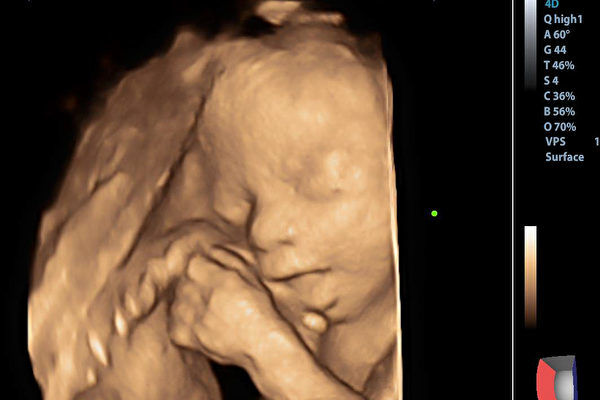

2024年10月初,侯女士注射了促排卵藥物。2024年10月底,侯女士成功懷孕了。2024年11月12日,經過醫院檢查,侯女士宮腔內顯示有九個孕囊。

去年11月14日,胡先生發聲,考慮到妻子的健康和撫養孩子的經濟成本,決定減胎。11月26日,胡先生發文稱已完成2次減胎手術,2個胎心還在搏動,希望孩子能順利平安出生。

據《南昌晚報》1月7日報導,胡先生披露,經過多次減胎後,侯女士腹中剩下的兩胞胎也保不住了。

胡先生表示,經檢查侯女士宮頸口縮短,一個胎兒的羊水破了,已經被感染;醫生稱另外一個胎兒也會被感染,而且,如果不將腹中的兩個胎兒去掉,將嚴重威脅侯女士安全。